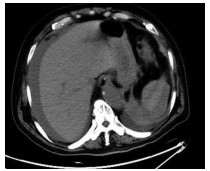

Primary biliary cholangitis with hepatic angiosarcoma: A case report

Jiamin ZHAO, Zhiyuan CHEN, Chengliang DING, Lili YUAN, Jingjing QIAN, Chunyang XU, Lingyun ZUO

2021, 37(10): 2411-2413. DOI: 10.3969/j.issn.1001-5256.2021.10.031

Abstract(818) HTML (189) PDF (2456KB)(80)

Abstract: